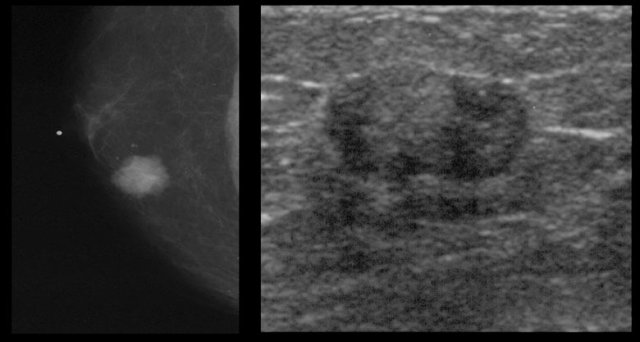

Mammogran and rotated ultrasound image Mammogran and rotated ultrasound image

Nodular pattern

The nodular pattern of gynecomastia is seen in the florid early phase.

It begins as an increased number of ducts and epithelial proliferation with edema and cellular fibroblastic stroma.

This phase is reversible.

On the left a mammogram and an ultrasound image of a patient with a nodular glandular pattern of gynecomastia.

Notice that it is situated underneath the nipple.

The ultrasound image shows the typical appearance of gynecomastia: a hypoechoic mass with lobulation or even spiculation.

If this was seen in a woman, you would say that this is a mass with microlobulation and spiculation, i.e. Birads IV or V.

In a man this is typical for gynecomastia.

On the left the same ultrasound image, but now in the normal position.

Notice how 'malignant' it looks.